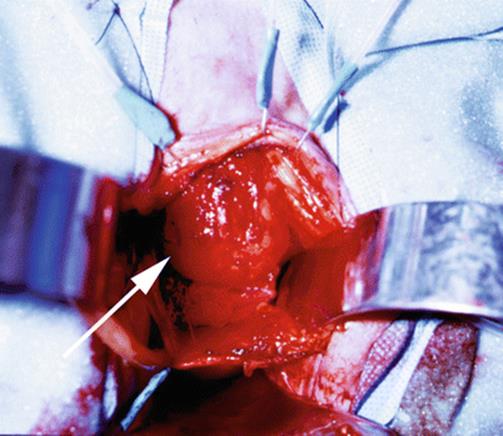

8.13 Large Urethral Leiomyoma Causing Urethral Obstruction

During her second pregnancy, the young patient in Figs. 8.43, 8.44, 8.45, 8.46, 8.47, 8.48, 8.49, 8.50, 8.51, 8.52, 8.53, 8.54, 8.55, 8.56, 8.57, and 8.58 presented with difficulty in voiding, tenderness in the anterior vaginal wall, and the feeling of a mass. Physical examination revealed a large, nontender, elastic, nonmobile mass inferior to the pubic bone. The mass displaced the urethra inferiorly.

Sagittal T2 MRI of the midpelvis reveals a large mass, mostly solid, with areas of necrosis and fluid displacing the anterior vagina and urethra inferiorly. The uterus is normal except for several small fibroids, and the adnexa are normal

Fig. 8.44

An axial MRI shows the replacement and displacement of the urethra by the large mass. Multiple areas of necrosis are seen. The arrows outline the tumor